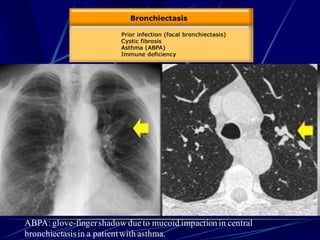

Bronchiectasis

Bronchiectasis is defined as localized bronchial

dilatation. (signet-ring sign)

bronchial wall thickening

lack of normal tapering with visibility of airways

in the peripheral lung

mucus retention in the broncial lumen

associated atelectasis and sometimes air

trapping

ABPA: glove-fingershadow dueto mucoid impaction in central

bronchiectasisin a patientwith asthma.